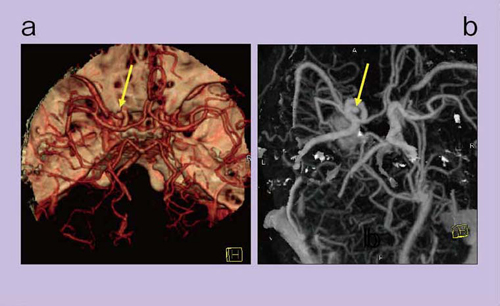

80kVの低電圧で撮影すると,造影剤(ヨード)や骨のCT値が持ち上がって,白く光って見える(図1)。DEイメージングでは,このCT値の持ち上がりの差を使って,いろいろな処理を行う。3D画像再構成(VR)では,細い血管や血管表面の滑らかさが,80kVの低電圧でコントラストを高くした方が明らかに優れていることがわかる(図1 右)。

図1 頭頸部のDEイメージング

頭頸部領域の骨除去にはDEイメージングのアルゴリズムのうち,Two-material decompositionを用いる。図3は,Lt- ICAの動脈瘤が疑われる症例のVR画像で,コンベンショナルCTA(a)では骨が重なり,動脈瘤の評価は困難であるが,DEイメージングではワンクリックで1分以内に,bのように骨除去された画像が簡便に表示される。骨除去CTAでは,動脈瘤の全体像がよく把握できる。

図3 頭部CTAのVR画像

a:コンベンショナルCTA

b:DE骨除去CTA

また,骨除去すると,VR画像のほかに,DSA様のMIP画像を作成することも可能である(図4 a)。

図4 DE骨除去CTAとDSA

a:DE骨除去CTAのMIP画像

b:DSA画像